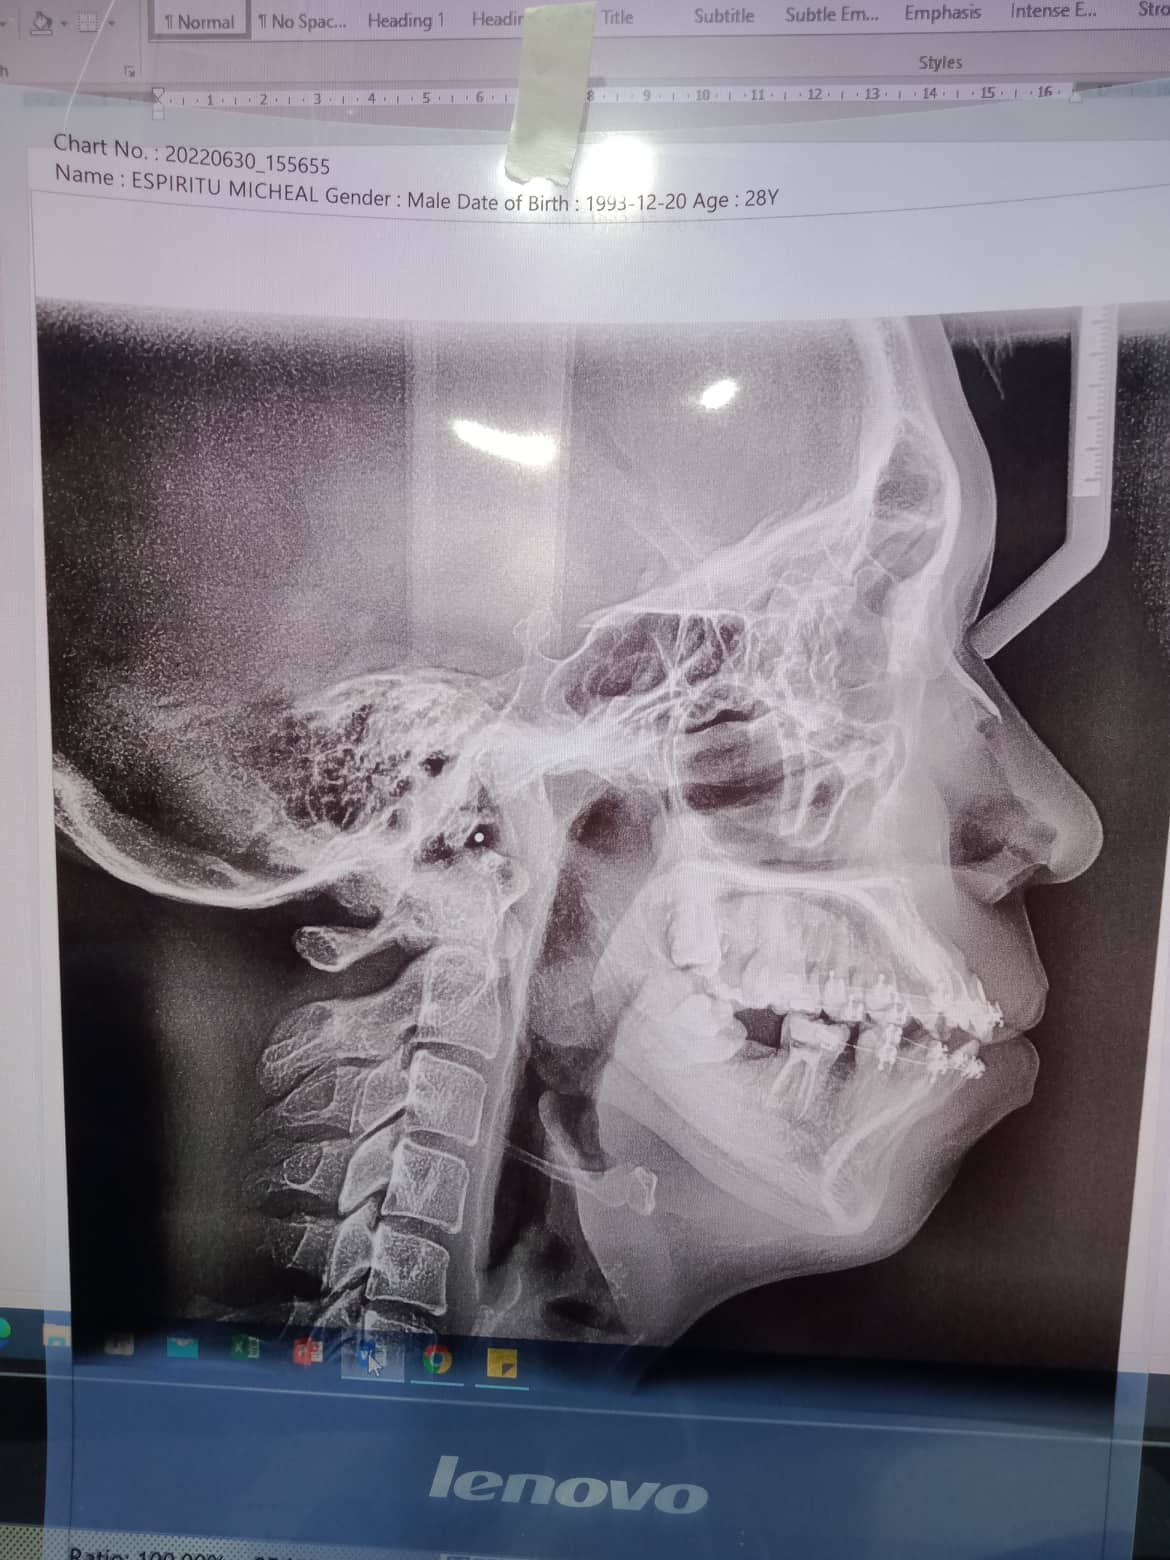

Edit Record Check our patient data records. Add patient information Patient Info Profile picture Last Name First Name Middle Name Birthdate Age Street Barangay City Country Zip Code Contact number Email Procedure 1/14/22- 12,22,36 - Xray LC # 26,27 & OP 1/29/22 - LC #12 - Mesial , lingual, labial LC#11 Surfaces mesial, distal, lingual, labial LC #21 - Mesial 2/19/22- exo 37 *for rct 4 canals 36 2/25/22 DB 21mm DL 22 mm MB 20.5mm ML 20mm formocresol with eugenol 2/05/22- camphenol/ white file *no sensitivity to hot and hold and during auscultation/ TF 2/12/22- no more pain. no more sensitivity/camphenol **next meeting xray. laser/ obturation 3/18/22- laser/ obturation/filling with fiber/ occlusal/ buccal/ lingual/mesial *observe 03/22/22- mbt 0.22/ 14 niti Ul/ class 3/ crowding ceph/ pano/ intraoral/ extra oral photos/ *** to ff up- cast analysis with ortho brush and wax 4/22/22- 14 niti UL RW #31 05/21/22 adj same wire/ req for ceph for exo Pm upper LR 7/2/22- Same wire 14 niti U/L RPI 22 Distal w/ RW Request Tad fot 4th Q 07/28/2022-U 0.016SS; placed ocs bet 11 and 13. L 0.016NITI; changed ligaties only. 08/27/22- SAME WIRE/ rpi 13/22 9/29/22 - RPI #21/#22, U 16ss wire, CHAIN #13-#15, INDIV #12-26; L SAME WIRE INDIV 11/04/22-ADJ/reattached 12/2/22- adj/1 reattached #36 01/13/23-adj 04/17/23- adj 16ss U indi/18 ss L chain 05/13/-23- U - same wire, individual/L - 16 ss, chain/Resto #11D class III 06/16/23- ortho UL same wire, U: individual L: chain RW # 31M 07/15/23- 18 ss U/ Rw 11M/ same wire lower chain lower closing space 08/15/23- closing space/ same wire ***for Lc 14/15/16 09/19/23- same wire/ chain upper/ chain 32-35 chain 11/12/24- ipr 11/21 DISTAL/ CLASS II ELASTIC chipmunk for TADS - 3500 01/27/24- same wire chain upper reattached # 02/28/24 -same wire -reattach #14 03/27/24 16x22 lower chain U RW #42 mesial for removal for the month of june 04/27/24 #14 reattached- no charge same wire chain U/ chain #33-34 05/28/24 16x22 U/L chain 32,34 class II elastic one quadrant II to III chipmunk 06/28/24 removal of brace File 300986490_754411172436439_2707532318128906720_n.jpg File 2 299958020_854700088834251_2016017323265959674_n.jpg File 3 302089664_596777748599375_6189577205987709592_n.jpg File 4 302471710_409703067737285_7864073801397539615_n.jpg File 5 302092198_453164560086776_1373823481126109582_n.jpg File 6 espiritu.jpg File 7 michael_espiritu.jpg File 8 michael_espiritu_1.jpg File 9 File 10 File 11 File 12 File 13 File 14 File 15 File 16 File 17 File 18 File 19 File 20 Retain Record Retain Record Yes No Save Your Changes